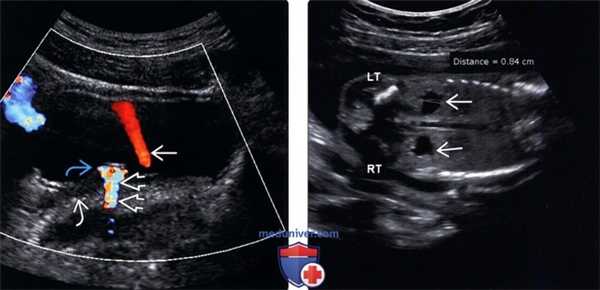

(Левый) На продольном трансабдоминальном ультразвуковом срезе визуализируется расширение чашечно-лоханочной системы почки. Выраженное истончение паренхимы указывает на длительно текущий процесс.

(Правый) На ультразвуковом срезе с цветовой допплерографией у того же пациента ИР = 0,7 (в пределах нормы), что согласуется с хроническим течением тяжелого гидронефроза у данного пациента.

(Левый) На поперечном трансабдоминальном ультразвуковом срезе мочевого пузыря с цветовой допплерографией визуализируется обтурирующий конкремент в правом МПС. Дистальнее конкремента визуализируется артефакт мерцания, который служит важным признаком конкремента в мочеполовом тракте. Наблюдается умеренная дила -тация мочеточника проксимальнее обтурирующего конкремента. На противоположной (левой) стороне визуализируется нормальный ток по мочеточнику.

(Правый) На фронтальном антенатальном УЗ срезе плода визуализируется двустороннее расширение чашечно-лоханочной системы (лоханка = 8 мм, в норме измеряется ПЗ размер на поперечном срезе).